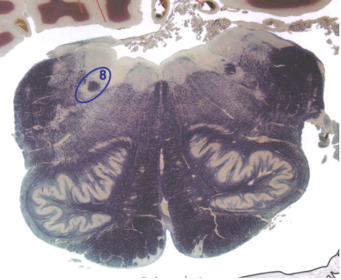

| Longitudinal pontine fibers (corticospinal tract) | |

| Transverse pontine fibers (dark fibers) | |

| Pontine nuclei (pale) | |

| Medial lemniscus | |

| ALS | |

| Trapezoid body | |

| Ventral trigeminothalamic tract | |

| Superior olive | |

| Central tegmental tract | |

| Facial nerve root fibers - descending | |

| Facial motor nucleus | |

| Interposed nuclei | |

| Medial longitudinal fasciculus | |

| Facial nerve root - internal genu | |

| Abducens nucleus | |

| Lateral vestibular nucleus | |

| Superior vestibular nucleus | |

| Inferior cerebellar peduncle | |

| Superior cerebellar peduncle | |

| Dentate nucleus | |

| Fastigial nucleus | |

| Anterior spinocerebellar tract | |

| Spinal nucleus of V | |

| Spinal tract of V | |

| Middle cerebellar peduncle | |